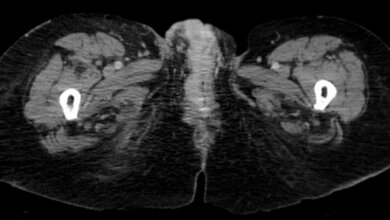

Um die Unsicherheiten der Schätzungen deutlich zu machen, wurden die Angaben als Spannen formuliert. Demnach werden von 1.000 Frauen, die im Alter zwischen 50 und 69 regelmäßig an der Mammographie-Früherkennung teilnehmen, 2 bis 6 durch den Test vor dem Tod durch Brustkrebs bewahrt. Dem steht als wichtiger Nachteil gegenüber, dass 9 bis 12 von 1.000 Frauen eine sogenannte Überdiagnose erhalten.

Mit dem Begriff Überdiagnose ist gemeint, dass bei einem Teil der Frauen Brustkrebs diagnostiziert wird, der ohne Früherkennungsuntersuchung nie aufgefallen und nie behandlungsbedürftig geworden wäre. Für diese Frauen wäre es also besser, wenn der Krebs gar nicht erst gefunden würde. Ein Grund: Es gibt kleine Tumore, die langsam oder gar nicht wachsen. Im Projekt bestätigte sich, dass viele Frauen noch nie von dieser Tatsache gehört hatten.